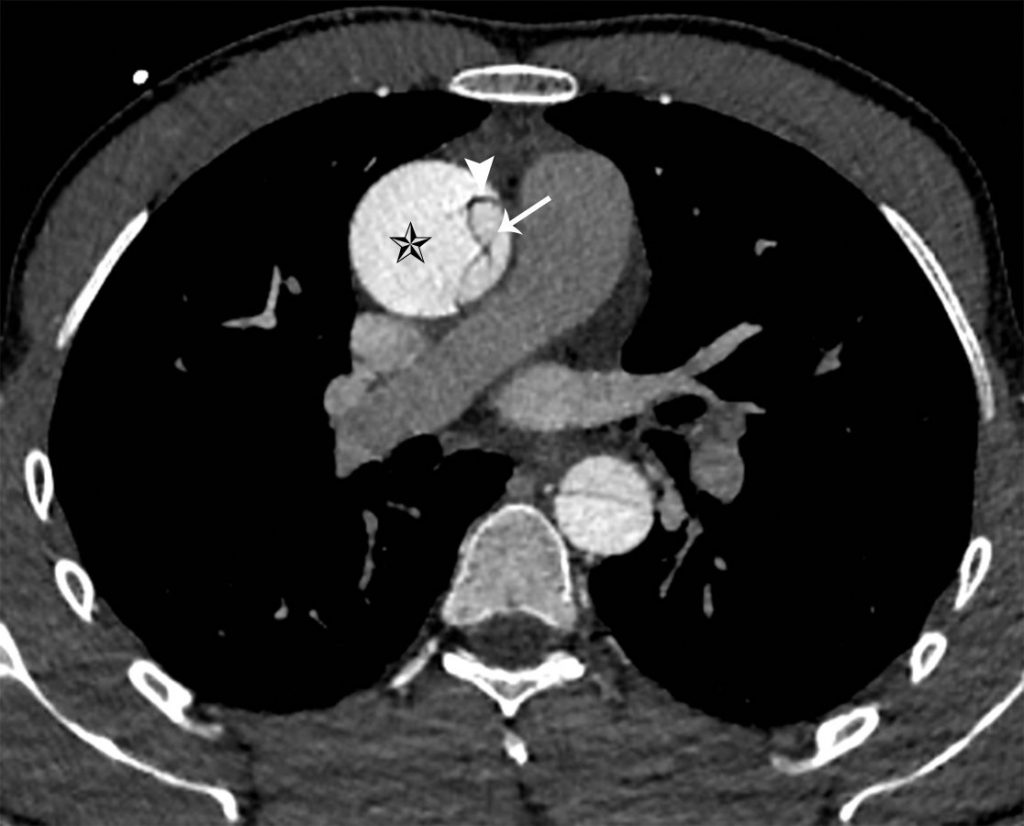

III. Sémiologie

La dissection apparaît, en échographie ou sur les coupes tomodensitométriques transversales injectées et les reconstructions sagittales, sous la forme d’un flap intimal qui divise l’artère en deux chenaux :

- le vrai chenal, qui communique avec la lumière aortique depuis le ventricule gauche ;

- le faux chenal, qui prend naissance sur l’aorte ascendante ou horizontale dans le type A (figure 36.7) et après la naissance de l’artère subclavière gauche dans le type B (figure 36.8). Il peut circuler plus lentement, voire se thromboser (responsable d’un hématome pariétal), comprimer ou pas le vrai chenal, ou subir dans le temps une évolution anévrismale.

Fig. 36.7. Angioscanner thoracique en coupe axiale d’un anévrisme de l’aorte ascendante associée à une dissection de type A avec un flap intimal (tête de flèche) dans l’aorte ascendante et dans l’aorte descendante, séparant le vrai (flèche) et le faux chenal (étoile).

Source : CERF, CNEBMN, 2022.